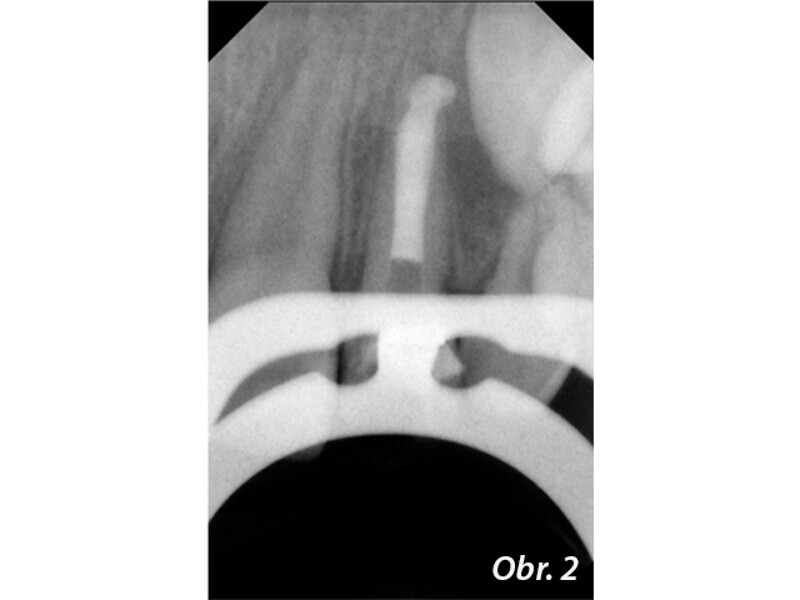

Endodontické ošetření zubů s nedokončeným vývojem kořene